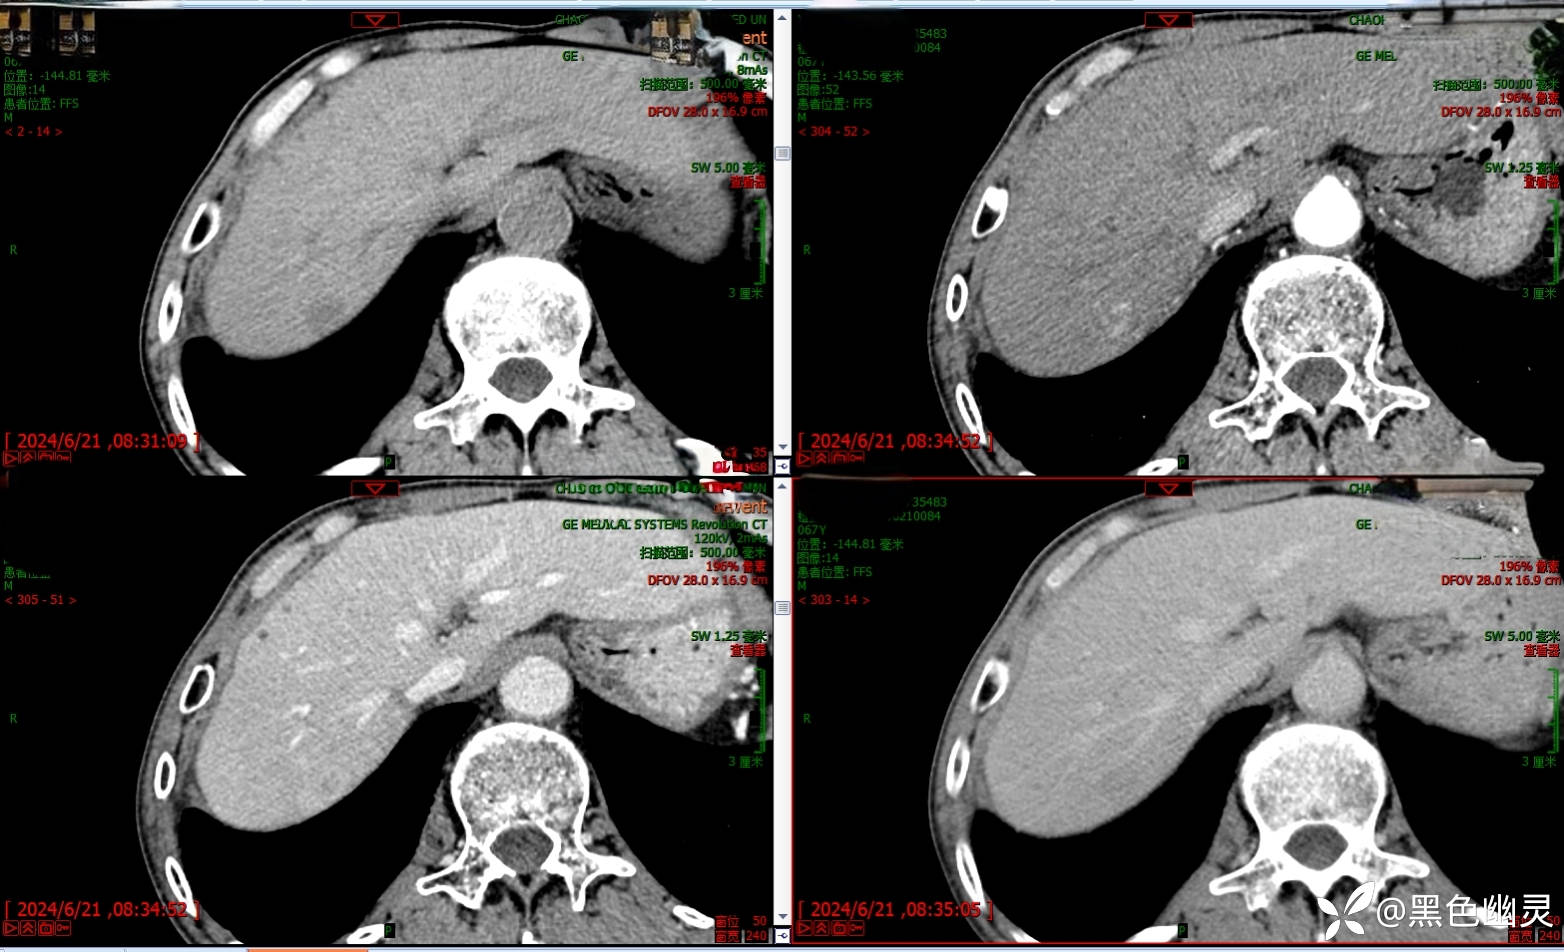

患者,男,68岁。1月前患者体检时发现肝脏右后叶结节,无腹痛、腹泻,无呕吐,无鼻塞、流涕,尿量正常,门诊拟肝右叶占位,收住我科。病程中患者一般情況尚可,无量减少,睡眠欠佳,大便基本正常,体重未见减轻。

查体,神清,全身皮肤巩膜无黄染,腹部压痛阴性,反跳痛阴性,双下肢无浮肿。